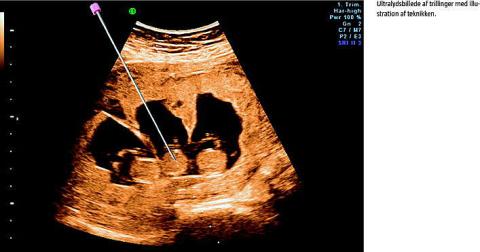

Ved fosterreduktion ombringes et eller flere fostre i et flerfoldsvangerskab selektivt. I Danmark gøres det ved injektion af kaliumklorid intratorakalt eller intrakardielt i fostret. Proceduren udføres transabdominalt og ultralydsvejledt, oftest omkring graviditetsuge 12. Fosterreduktion kan foretages for at mindske de risici for komplikationer, der er forbundet med flerfoldsgraviditeter [1], herunder præmaturitet, abort, dødfødsel, lav fødselsvægt, neonatal mortalitet og morbiditet [2, 3]. Fosterreduktion kan desuden udføres, hvis der konstateres alvorlig sygdom hos det ene foster [4].

Det seneste årti er der kommet mere debat om og fokus på fosterreduktion. De fleste har accepteret brugen af fosterreduktion ved firlinger eller flere fostre, da risikoen for komplikationer nedsættes betydeligt [5]. Den væsentlige debat omhandler fosterreduktion af trillinger og tvillinger [6, 7]. Senest har Etisk Råd udbedt sig en undersøgelse af omfanget af reduktionerne [8].